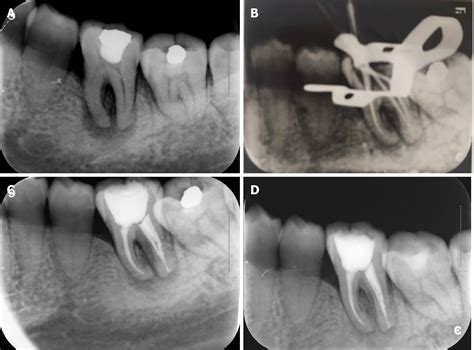

• Root Canal Planning: To visualize the shape, length, and condition of the root canals before performing a root canal treatment.

How the Procedure Works

The process for taking a Periapical X Ray is straightforward, quick, and generally painless. Modern dental offices have transitioned almost entirely to digital radiography, which makes the process even faster and safer than traditional film methods.

1. Preparation: You will be given a lead-lined apron to wear, which protects your body from unnecessary radiation exposure.

2. Sensor Placement: The dental assistant or technician will place a small, digital sensor (or film) inside your mouth, positioned directly behind the tooth or teeth being imaged.

3. Positioning: The X-ray machine head is positioned carefully near your cheek, aimed precisely at the sensor.

4. Exposure: You will be asked to hold still while the X-ray machine emits a brief, low-dose burst of radiation. This takes less than a second.

5. Processing: With digital X-rays, the image appears almost instantly on the dentist's computer monitor, allowing for immediate analysis.